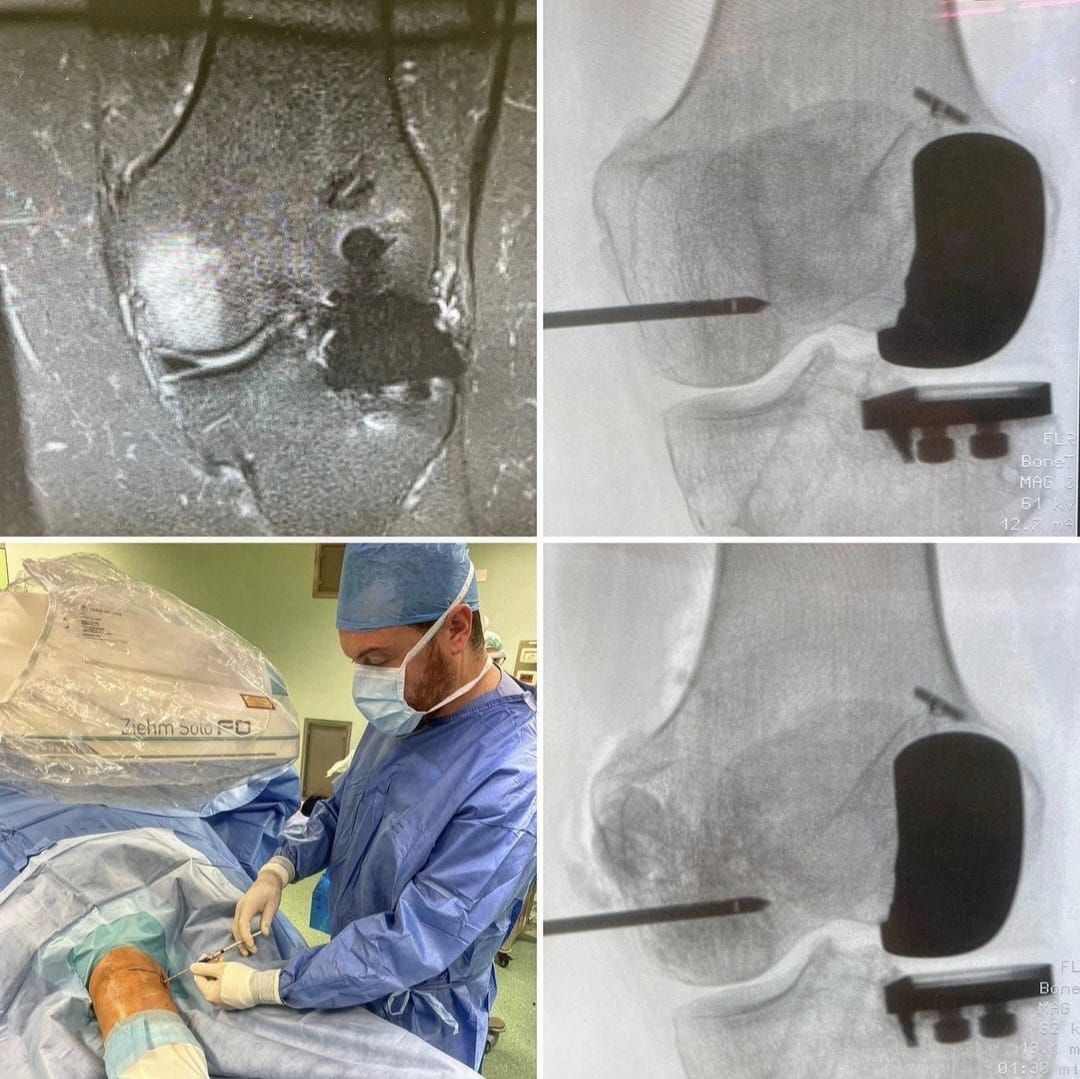

Sia l’aspetto dei materiali utilizzati sia l’aspetto delle tecniche chirurgiche garantiscono al paziente i massimi standard qualitativi, è però una mia profonda consapevolezza che il gesto chirurgico aiuta il paziente ma non è necessariamente l’unica scelta o la più appropriata, ed è per questo che mi sono e mi sto dedicando anche alla medicina rigenerativa, che reputo il nuovo orizzonte nel campo ortopedico per il trattamento delle patologie degenerative articolari.

Sono infatti il responsabile del gruppo C.A.S.C.O. dell'IRCCS Ospedale Galeazzi - Sant'Ambrogio di Milano per la medicina rigenerativa.